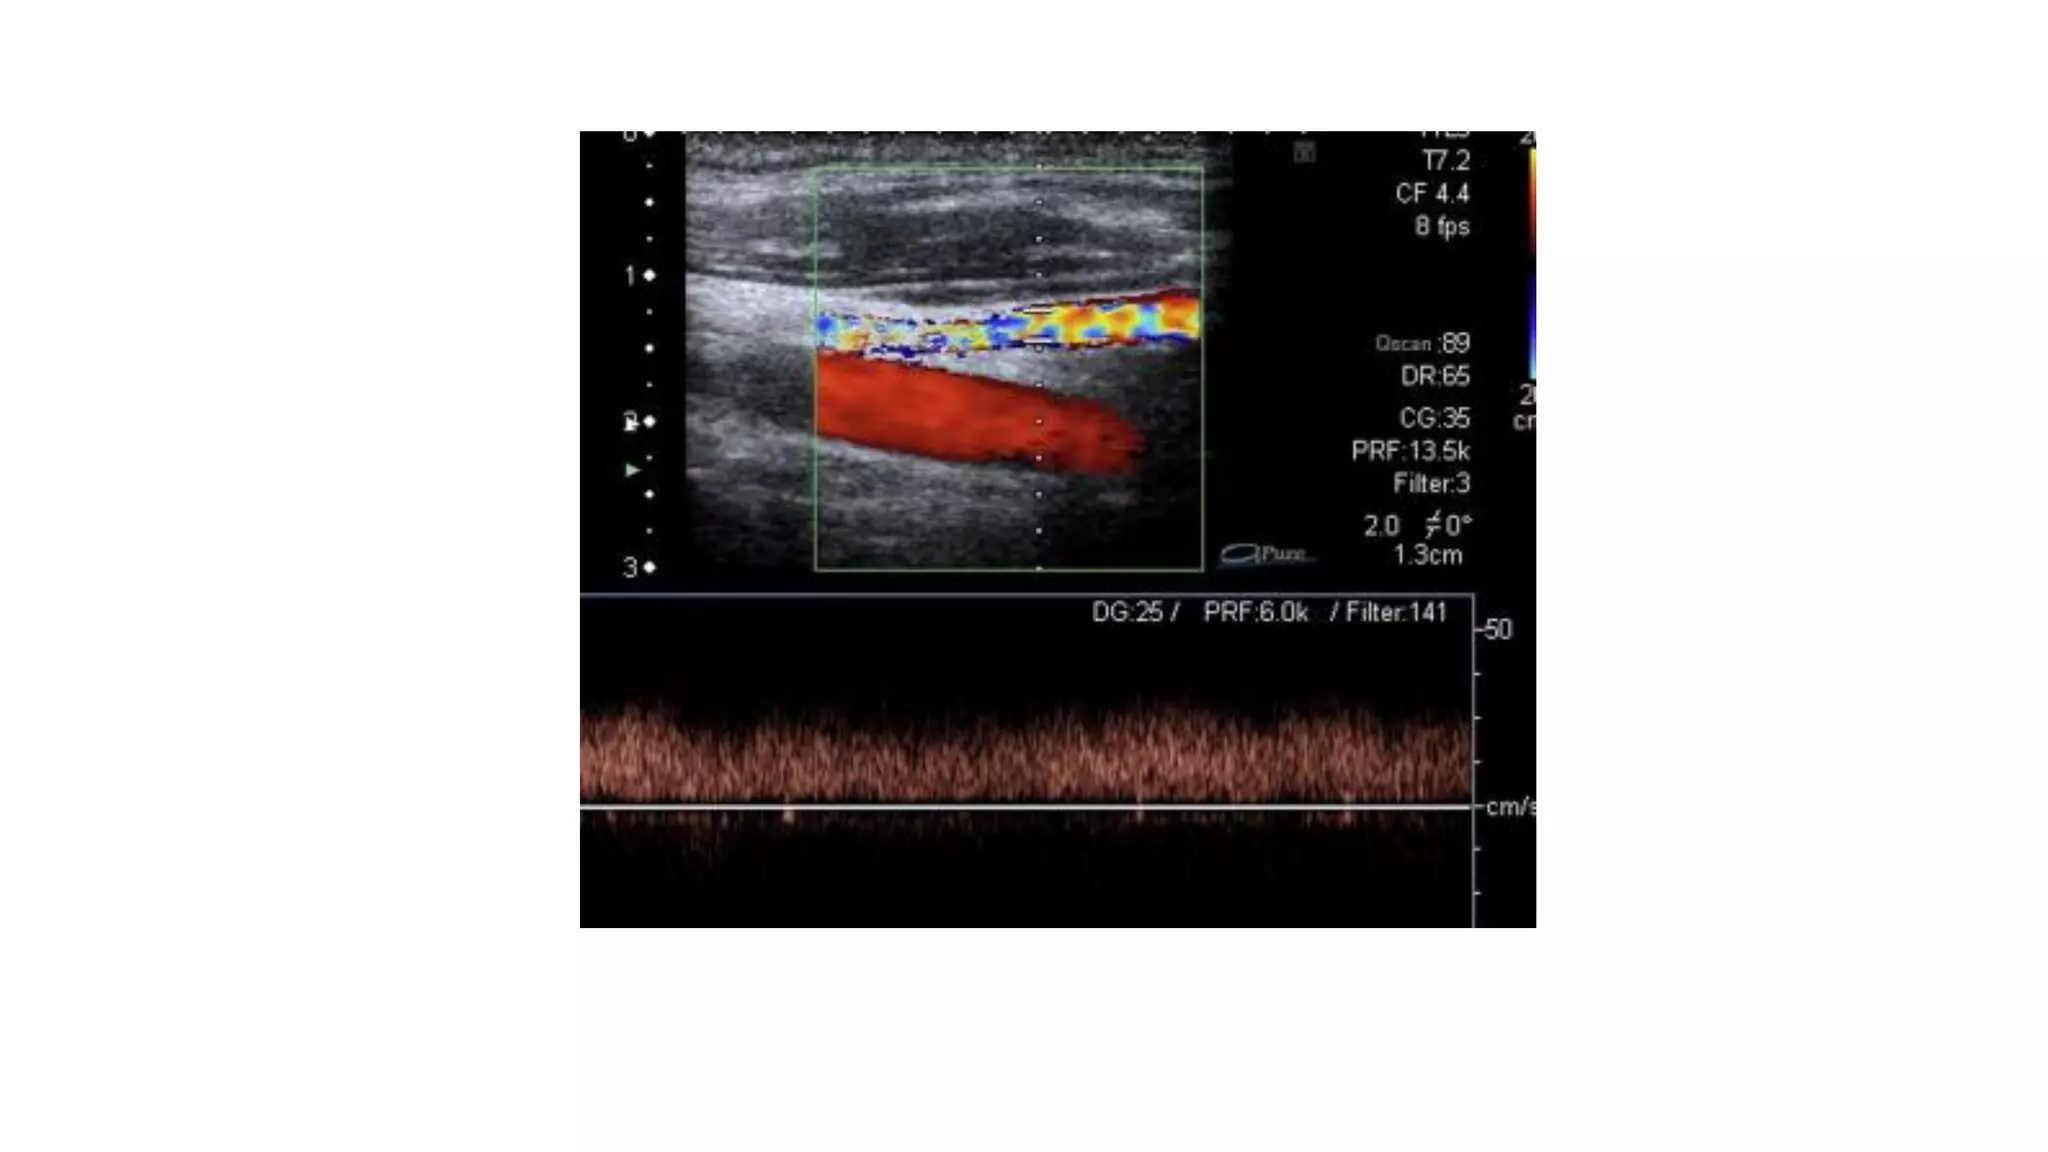

Ultrasound vascular mapping uses ultrasound to examine arteries and veins in the arms before dialysis access placement. It assesses vessel diameter, wall characteristics, blood flow, compressibility, and identifies the best vessels. The mapping examines arteries for internal diameter and wall appearance, uses Doppler to evaluate blood flow, and may check for calcification. It also assesses superficial arm veins for caliber, depth, wall appearance, distensibility, course, patency, and presence of collaterals to identify the best vessel options for dialysis access. A vein mapping worksheet is used to report the ultrasound findings.